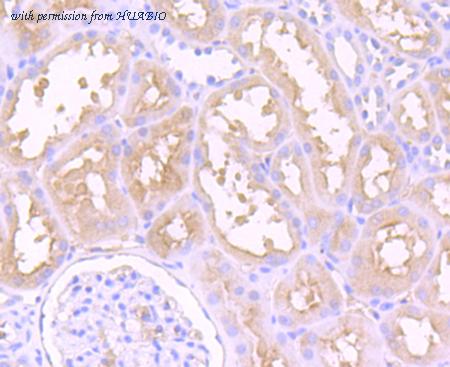

image 2 :

Immunohistochemical analysis of paraffin-embedded human kidney tissue using anti-Dysferlin antibody. Counter stained with hematoxylin.